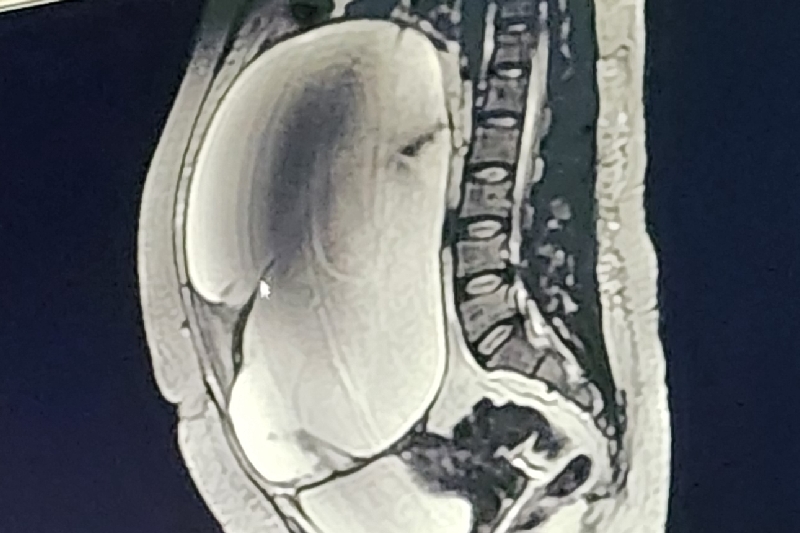

My daughter, Francesca, 37 a single mother of one has been diagnosed with a enormous ovarian cyst that has a high possibly of malignancy. She must undergo surgery to remove the 13 inch by 11 inch mass that will put her out of work for six to eight weeks if the surgery goes as planned. It will take several more weeks for her to get back on her feet due to the size of the mass. She is a wonderful young lady whose passion, when not working to support her child, is to spend time with her seven year old son at the park. She actively assist me with the daily activities of my 92 year old mother suffering from extreme dementia.